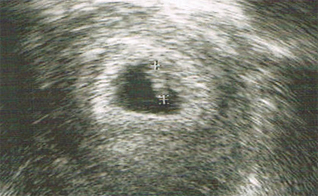

erstes Ultraschallbild

Bei den ersten zwei Frauenarztterminen muss ich lange warten und bekomme jedes Mal Blut abgenommen. So richtig spannend ist das Ultraschallbild – darauf bin ich total scharf. Als ich es dann sehe, ist das alles irgendwie ein bisschen irritierend, da ich noch nicht lange weiß, dass ich schwanger bin.

So unheimilch und aufregend schön zugleich. „Frau Wilde, Sie haben Glück, mit 35 Jahren werden Frauen nicht mehr so schnell schwanger.“ Dann lächele ich in mich hinein und überlege mir, dass ich sowieso keine alltägliche 35-jährige bin.

zweites Ultraschallbild

27. September 2011. Zu Hause öffne ich immer wieder meinen Mutterpass und hole die Ultraschallbilder heraus. Mein Schatz freut sich bereits im Büro darauf, die „Fotos aus dem Bauch“ zu sehen. Obwohl zwischen den zwei ersten Untersuchungen eine Woche liegt, erscheint es mir auf dem Ultraschallbild so, als hätte sich die Größe unseres Babys innerhalb einer Woche verdoppelt. Na ja, ich bin eben ne gute Esserin.